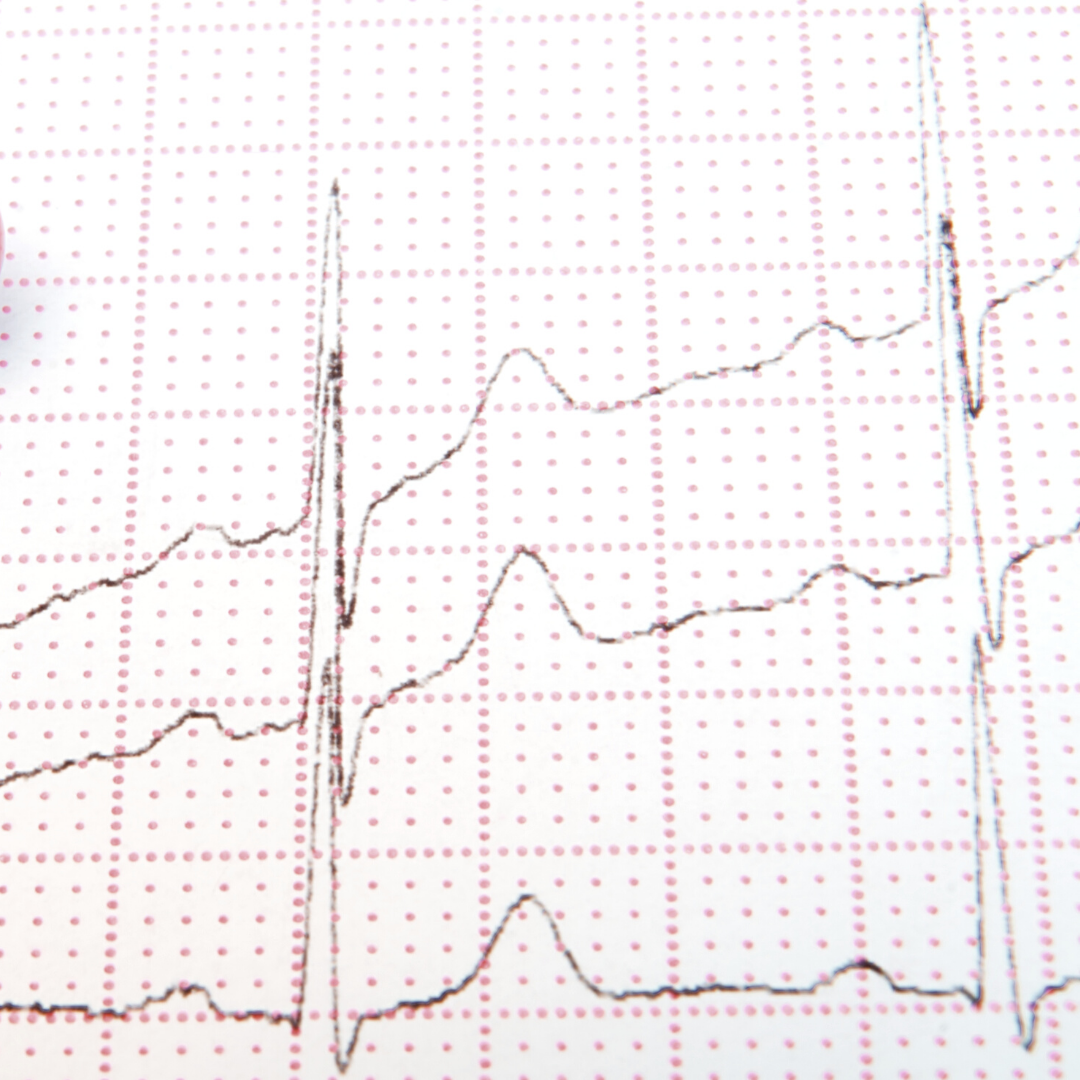

HRV is a measure of the difference in time between the beats of your heart. If you have a resting heart rate of 60 beats per minute, that doesn’t mean that your heart beats once every second. Instead your heart might beat at 0.9 seconds, then 1.4 seconds, then 1.1 seconds, and so on. HRV records the variability between beats, the difference between the shortest and the longest beat.